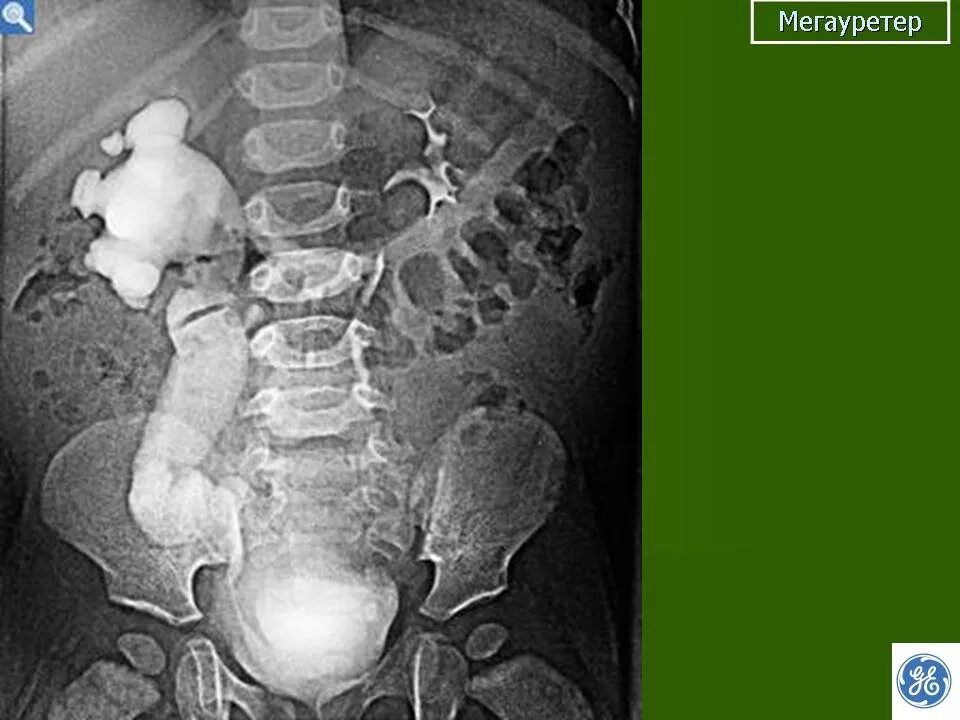

Мегауретер у детей что это